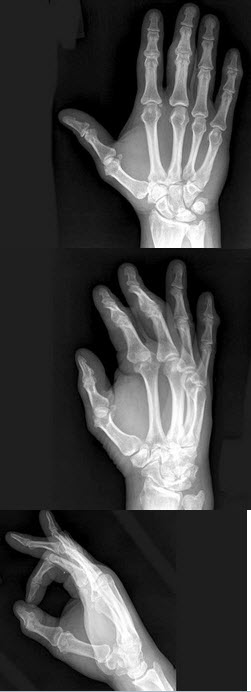

251、单项选择题

男,24岁,双手疼痛,结合图像,最可能的诊断是()

A.肢端肥大症

B.骨质疏松症

C.类风湿关节炎

D.痛风

E.维生素D缺乏症